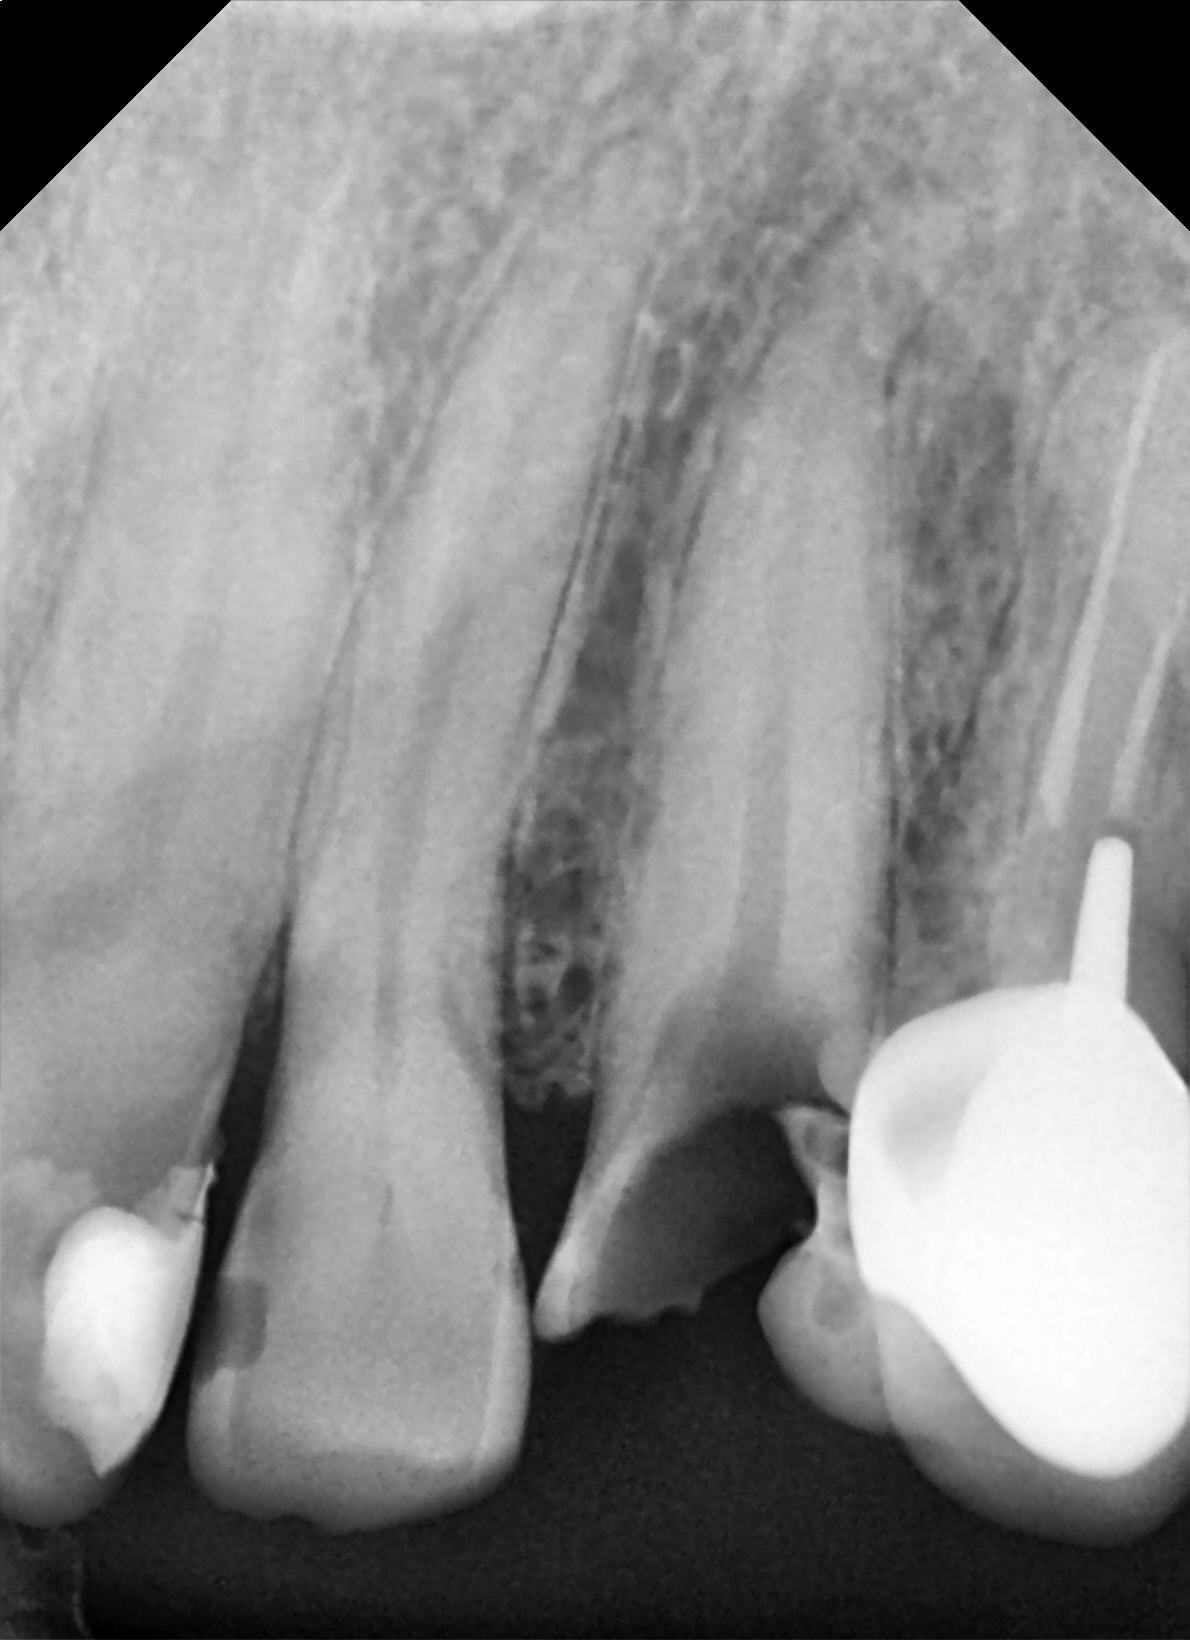

Je crois bien que je viens de visser un 23 dans la racine d'une 22...

- pas de retro de contrôle premier foret en place alors que la 22 à une racine en banane.

Pourrais tu mettre en' ligne mes radio pré-op (per-op?) et post-op ?

donc cas facile :

il viens initialement pour un devis brg 24 à 22.

Je lui fait une proposition impl+ccm en 23 superdiscount et banco. et un autre pour 25 26 16 . 27 et 17 devront être extraite et remplacés dans les 5 ans je pense

Jour de chir. Je lui pose donc une vis ( tiens autre erreur, c'était ma première avec ce système qu'utilise mon associé ).

Le capteur (visiodent ) salle de chir déconne----> pas de foret en place.

Visiblement les forets sont bien taillant, j'ai rien senti.

pose d'un 3.5 11.

-erreur d'axe super classique.

-nouveau ( pour moi ) système

-trop " cool " j'étais pas à ce que je faisais...

bref .. de la merde, depuis l'indication jusqu’à la pose :)

Je t'ai mis la rétro avec le débris de 23 et celle avec le piercing de 22 :)

Concernant ce type d'erreurs, voici quelques images trouvé sur Eugenol…

Mais il y a apparemment une erreur de parallaxe, qui elle est systématique! Le seul moyen d'y remédier étant de faire une radio tuteur en place…